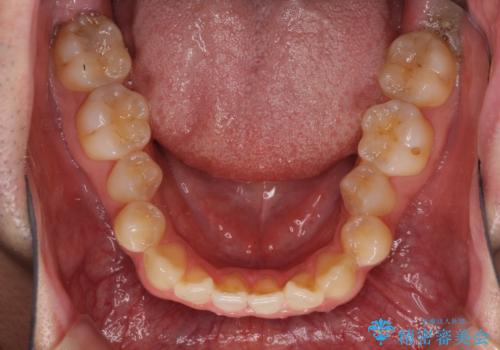

左右の八重歯が気になる ワイヤー装置での咬み合わせ改善

- 八重歯と前歯のデコボコを気にして来院された患者様です。

舌の突出癖がなかなか改善されず、上下前歯部の接触が得られるまでに予定の倍ほどの期間がかかりました。